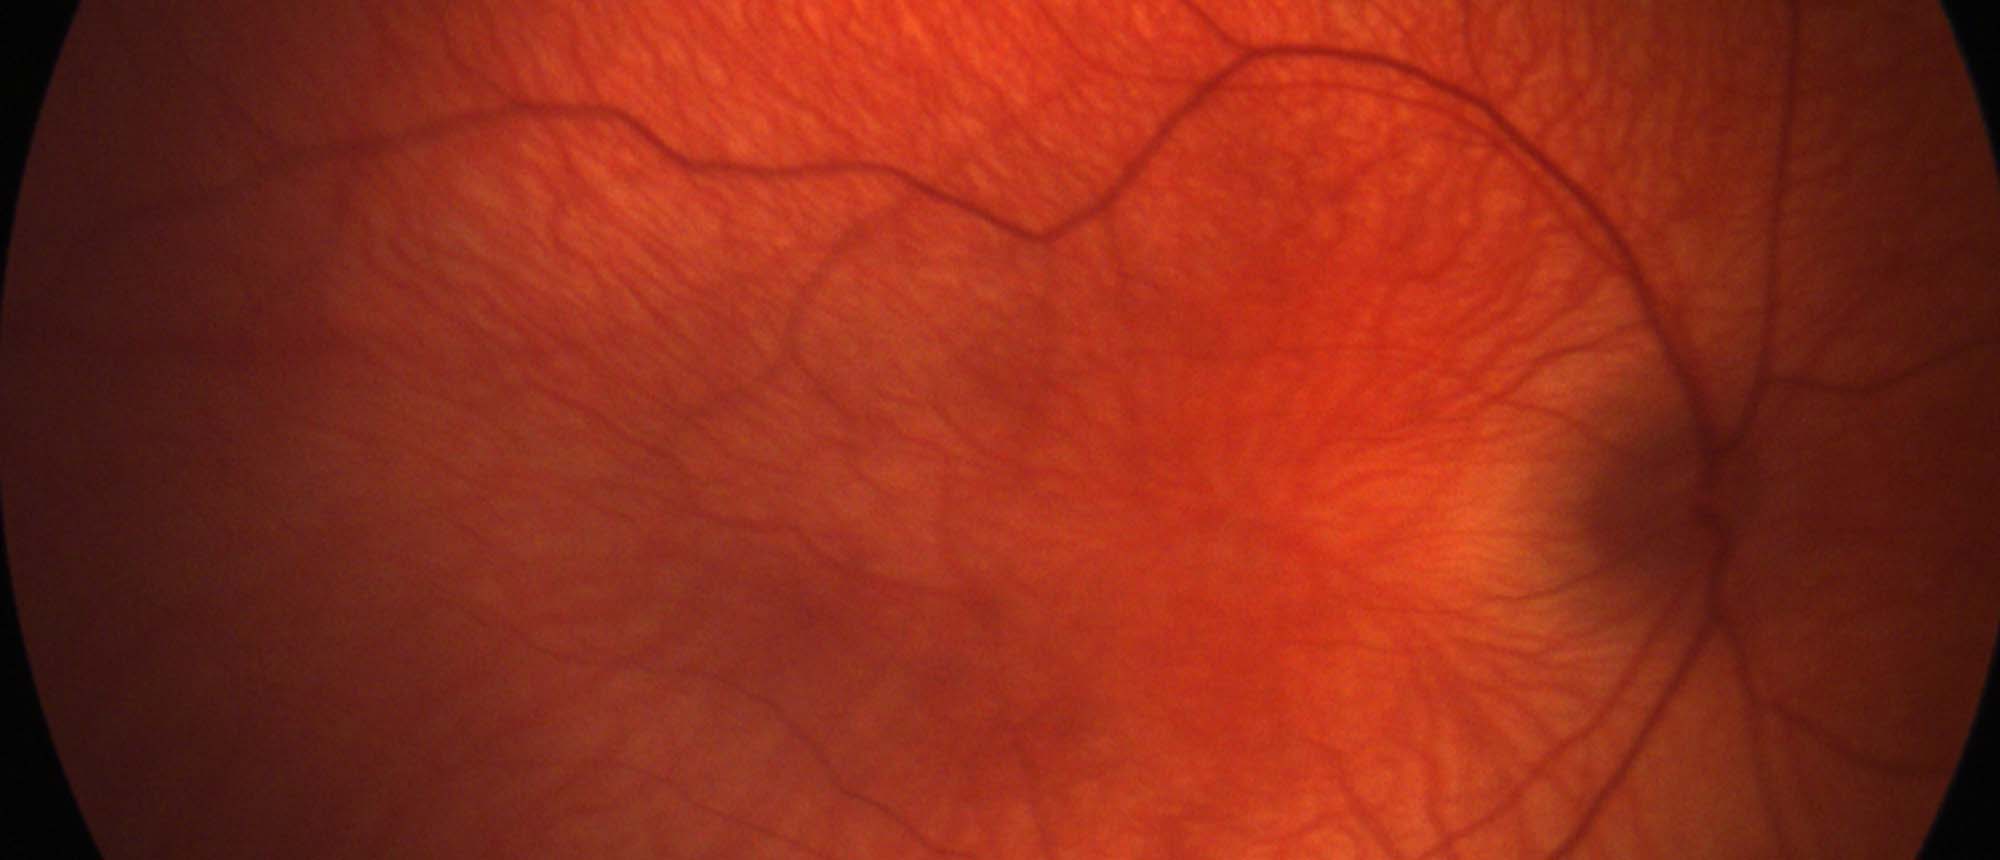

Fundus photo of Central Retinal Artery Occlusion (CRAO).